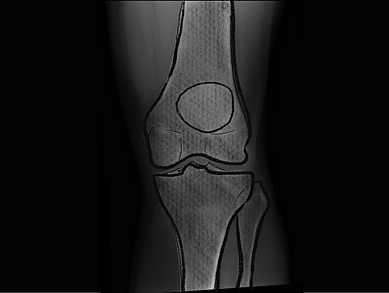

Total knee replacement

Experience the benefits of robotic knee replacement, offering accuracy and improved joint function for long-term relief.